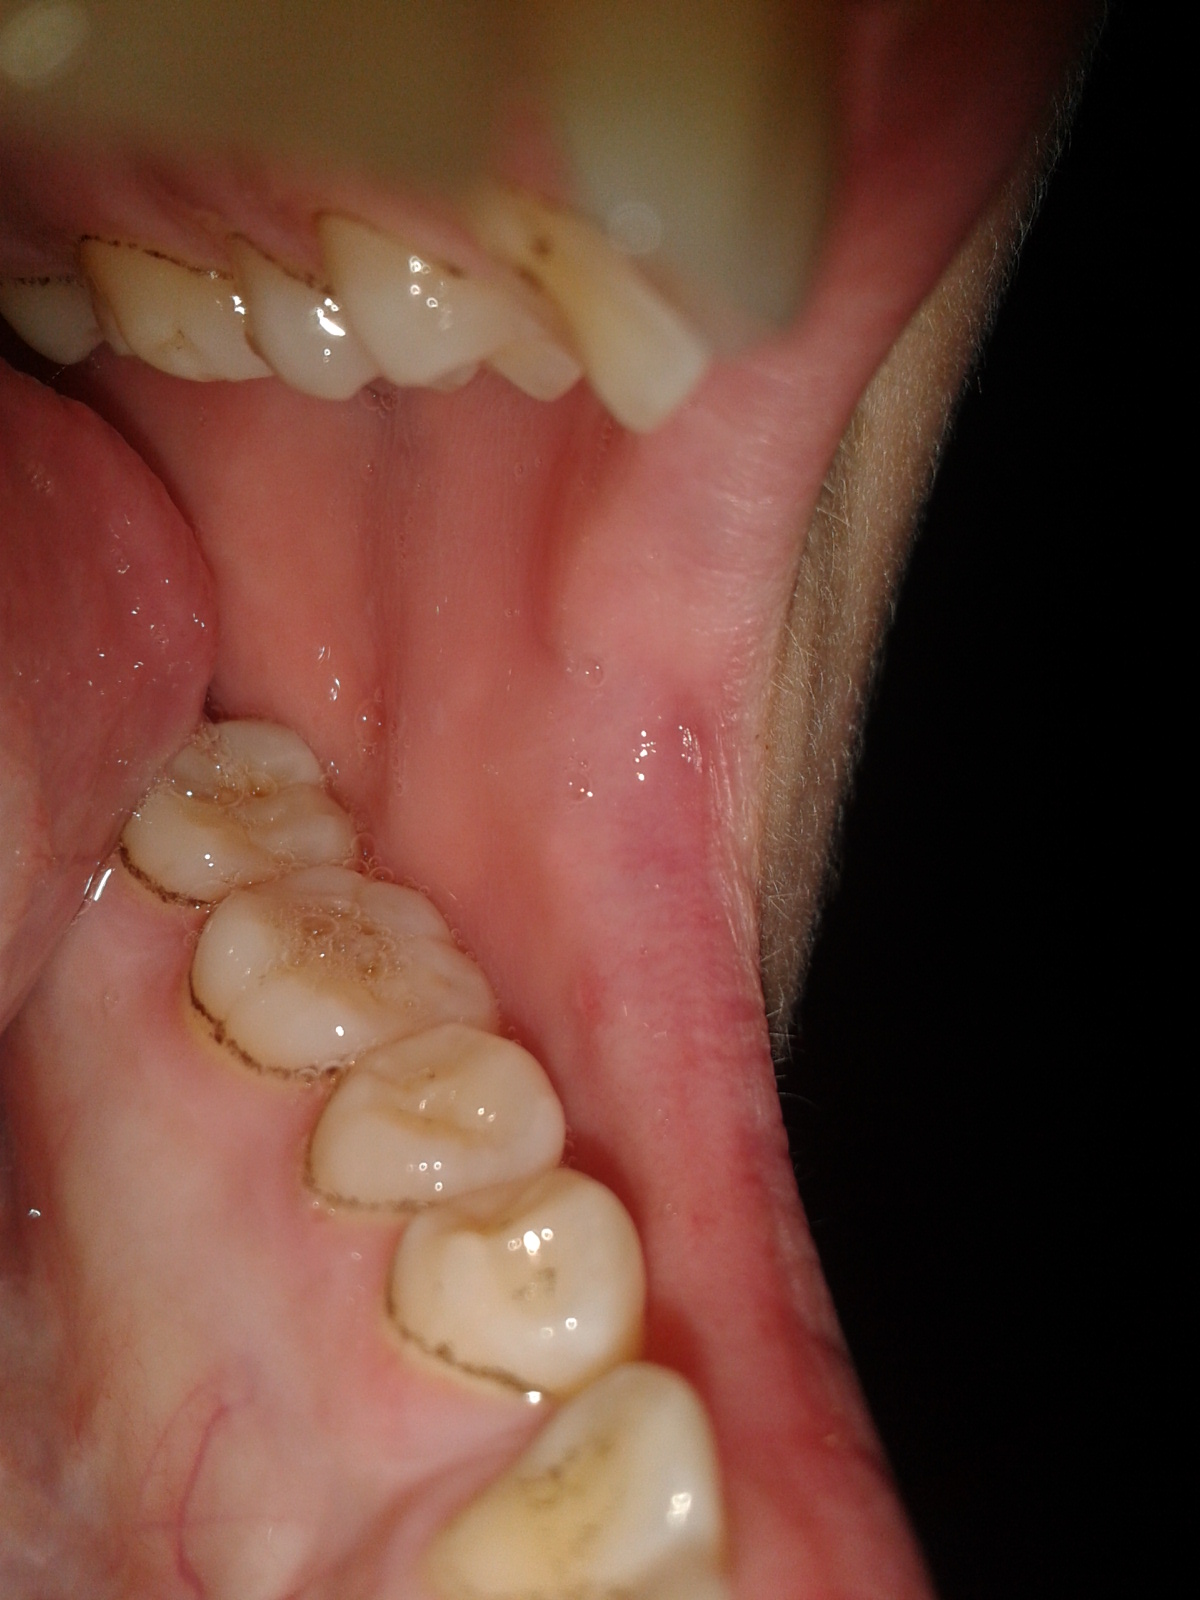

zahnstein entfernen schwarzer zahnreinigung können instrument praktischen hause hochwertiges führen 5er bequem etui zahnstein emedi symbolbild